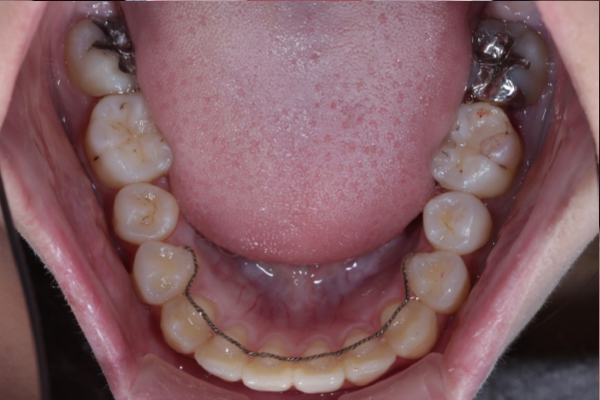

AFTER

埋まっている犬歯の牽引

残存していた乳犬歯を抜歯後、埋伏している上顎犬歯に対して外科的開窓を行い、矯正装置を用いた牽引を開始しました。

歯列に大きな叢生が認められなかったため、全体的な歯列バランスを維持しながら、スペース管理を行い慎重に犬歯の誘導を進めました。

定期的に歯の移動方向や歯周組織の状態を確認しながら治療を行いました。